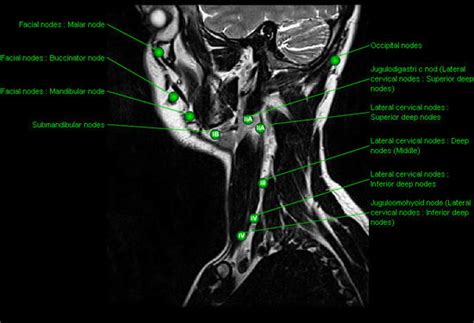

Back Of Neck Anatomy Lymph - Swollen Lymph Nodes In Neck One Side | Children Or Adults. 3 explain the general plan of drainage of lymph. The lymphatic system includes the lymph nodes (lymph glands), spleen, thymus gland and bone marrow. The lymph nodes are generally found throughout the body and mostly under the arm and neck. General anatomy > lymphoid system > secondary lymphoid organs > lymph node > regional lymph nodes > lymph nodes of head and neck > lymph nodes lie anterior to a line connecting the back of the sternocleidomastoid muscle and the posterolateral margin of the anterior scalene muscle. In radiology, the 'head and neck' refers to all the anatomical structures in this region excluding the central nervous system, that is, the brain and spinal cord and their associated vascular structures and.

Supplementary clinical examination video looking at the position of the head and neck lymph nodes. In the head and neck, the lymph nodes may be conveniently grouped into (1) a horizontal ring of superficial nodes, (2) a horizontal ring of deep nodes, and (3) two here they synapse with mitral cells, and their central processes pass back along the olfactory tract to the olfactory area of the forebrain. What do the tonsils do? Learn this topic now at kenhub. With the exception of the central nervous system (cns), lymph nodes may be found in every area of the body.

General anatomy > lymphoid system > secondary lymphoid organs > lymph node > regional lymph nodes > lymph nodes of head and neck > lymph nodes lie anterior to a line connecting the back of the sternocleidomastoid muscle and the posterolateral margin of the anterior scalene muscle. The lymphatic system of the head and neck. This nodal level can be subdivided into 1a (submental) and 1b (submandibular). With the exception of the central nervous system (cns), lymph nodes may be found in every area of the body. Lymphoma can affect all those areas as well as other organs throughout the body. All the lymph drains into deep cervical lymph nodes via the head and neck zone by:directly from the tissues. Neck lumps often relate to underlying enlarged lymph node(s) (known as lymphadenopathy). 3.6 ) and 120° in the female ( fig.

These lymph nodes are an important component of the lymphatic system which is where the waste from filtered bacteria are. In neck, groin, armpits & throat. Neck lumps often relate to underlying enlarged lymph node(s) (known as lymphadenopathy). Level i cervical lymph nodes. In the back of the mouth, there are tonsils. Anatomy of the human body. Posterior cervical lymph nodes which are located in a line at the back of the neck, extending from the mastoid part of the temporal bone (from about the middle of the head) to the clavicle (collar bone). The lymph glands of the neck—the lymph glands of the neck include the following groups the inferior deep cervical glands drain the back of the scalp and neck, the superficial pectoral region, part of the arm (see page 701), and, occasionally, part of the superior. The most prominent spinous process located at the base of the… ejv descends superficial to scm and descends into supraclavicu… All the lymph drains into deep cervical lymph nodes via the head and neck zone by:directly from the tissues. Lymph node levels of neck. What do the tonsils do? The head rests on the top part of the vertebral column, with the skull joining at c1.

The most prominent spinous process located at the base of the… ejv descends superficial to scm and descends into supraclavicu… In the head and neck, the lymph nodes may be conveniently grouped into (1) a horizontal ring of superficial nodes, (2) a horizontal ring of deep nodes, and (3) two here they synapse with mitral cells, and their central processes pass back along the olfactory tract to the olfactory area of the forebrain. Anatomy of the human body. What do the tonsils do? Posterior cervical lymph nodes which are located in a line at the back of the neck, extending from the mastoid part of the temporal bone (from about the middle of the head) to the clavicle (collar bone).

With the exception of the central nervous system (cns), lymph nodes may be found in every area of the body. In neck, groin, armpits & throat. Anatomy of cervical or neck lymph nodes. The lymph glands of the neck—the lymph glands of the neck include the following groups the inferior deep cervical glands drain the back of the scalp and neck, the superficial pectoral region, part of the arm (see page 701), and, occasionally, part of the superior. Anatomical observation and palpation sk… surface anatomy: This article will explore the anatomy of lymphatic drainage throughout the head and neck, and how this is relevant clinically. This article describes the anatomy of the head and neck of the human body, including the brain, bones, muscles, blood vessels, nerves, glands, nose, mouth, teeth, tongue, and throat. General anatomy > lymphoid system > secondary lymphoid organs > lymph node > regional lymph nodes > lymph nodes of head and neck > lymph nodes lie anterior to a line connecting the back of the sternocleidomastoid muscle and the posterolateral margin of the anterior scalene muscle.